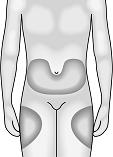

The best injection sites (see pictures below) are:

your abdomen, except for the area around the navel (belly button) or

the top and side of your thighs.

Change the place that you inject each time so you do not become sore in one area. If someone else is injecting you, they can

also use the back of your arms.

The best injection sites (see picture) are:

your abdomen, except for the area around the navel (belly button) or

the top and side of your thighs.

Change the place that you inject each time so you do not become sore in one area. If someone else is injecting for you, they

can also use the back of your arms.